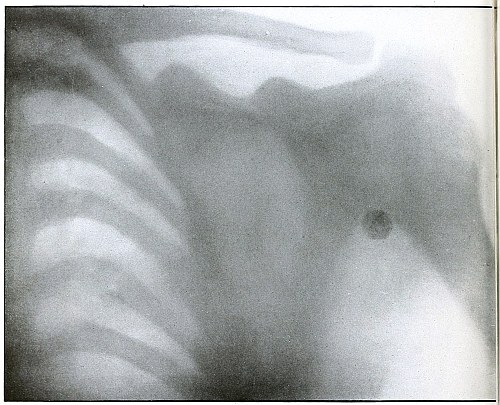

| 82.[Pg 5] |

Gunshot wound, shoulder |

174 |

| 83. |

Gunshot wound, shoulder |

176 |

| 84. |

Gunshot wound, shoulder |

178 |

| 85. |

Gunshot wound, shoulder |

180 |